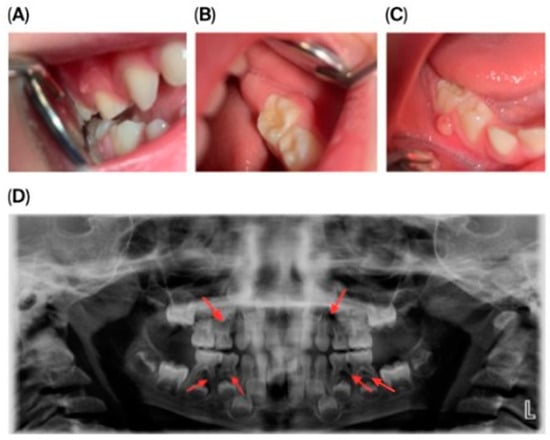

A laser-sintered digitally designed space maintainer was fabricated and cemented to preserve arch integrity and guide the eruption of the permanent successor (tooth 45) (Figure 3). Ongoing monitoring includes dental, biochemical, and renal assessments every 3–6 months.

Figure 3.

Orthodontic management following extraction of mandibular right second primary molar (tooth 85). (A) Scanned models of the dental arch showing the area of extraction and planned space maintenance. (B) Indirect intraoral mirror photograph showing the laser-sintered, digitally designed space maintainer cemented in situ to preserve arch integrity and guide eruption of the permanent successor (tooth 45). (C) Indirect intraoral mirror photograph showing a lateral view of the space maintainer, illustrating its position and adaptation to the adjacent teeth.

The extracted lower right second primary molar (tooth 85) is shown in Figure 4, demonstrating the extent of periapical pathology, with more than two-thirds resorption of the mesial root and structural changes.